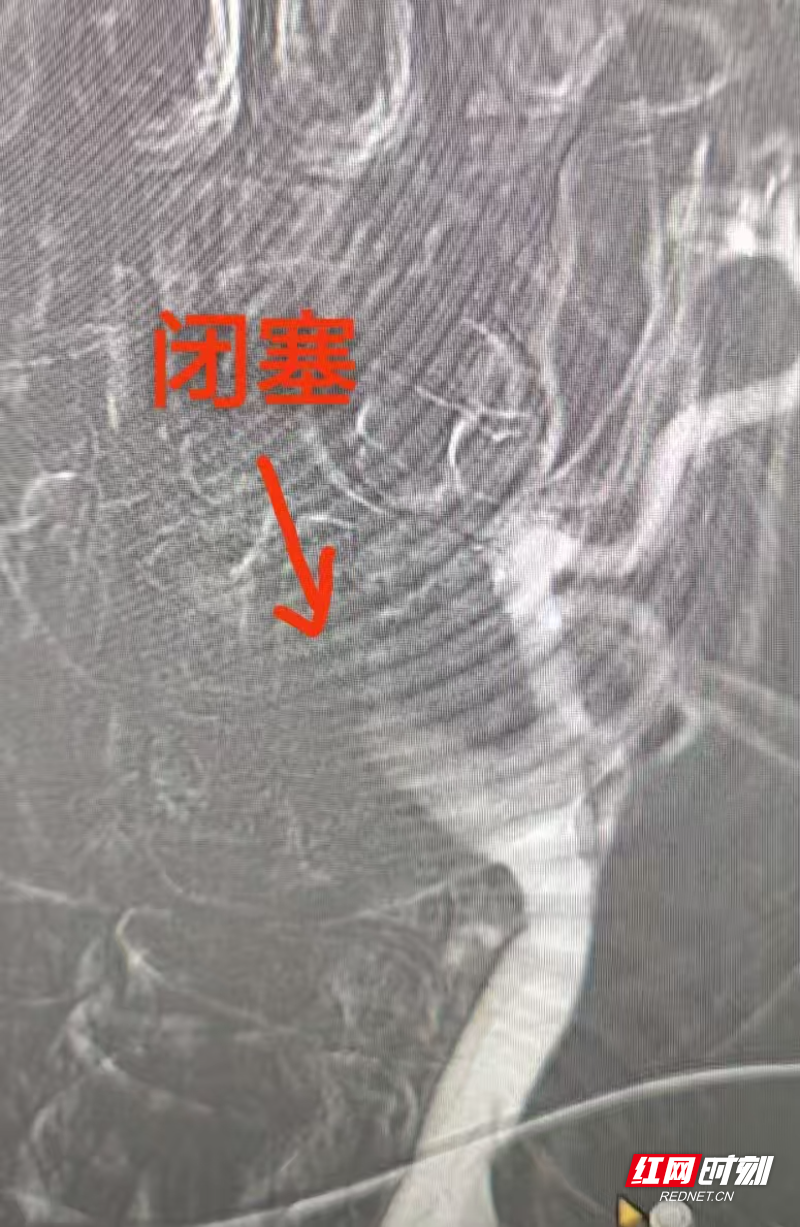

授权即行动!卒中中心绿色通道全程开启,患者第一时间接受静脉溶栓。与此同时,主治医师迅速开展急诊血管内介入手术。造影证实“左侧颈内动脉急性闭塞”,团队立即行颈动脉再通,利用微导丝、球囊精准开通血管。术后影像显示:血流恢复通畅!